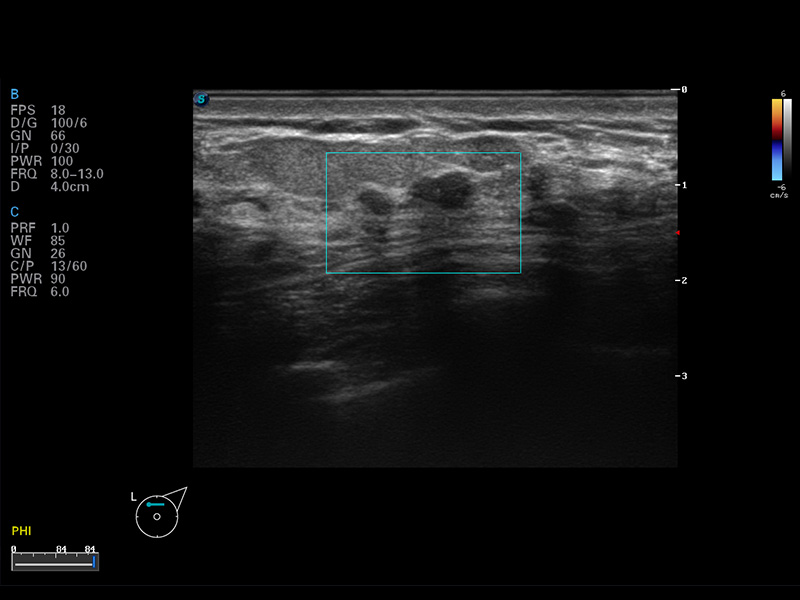

S8 EXP便携式彩色多普勒超声诊断仪是环球UG官网研发的高端全身应用型便携彩超。高通道的VIS平台融合可视化(Visual)、智能化(Intelligent)和人性化(Smart)的特点,配以环球UG官网自主研发生产的探头大家族,使您能够快速、准确的获得病人信息,提高工作效率的同时减轻疲劳。

成像技术

μ-Scan微米成像

谐波成像

空间复合成像